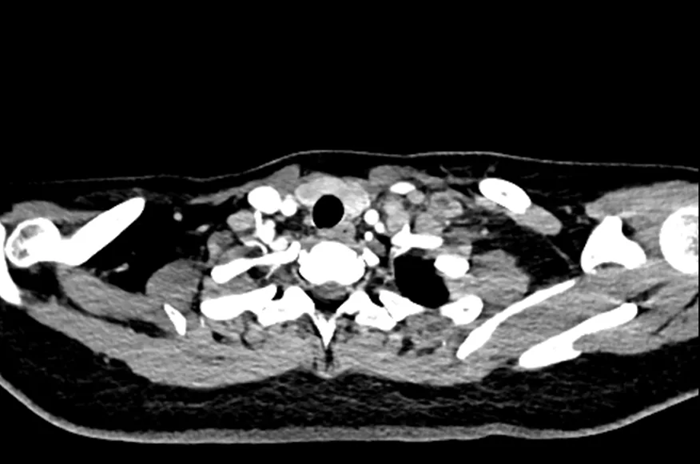

Hình ảnh chụp CT của nữ sinh 20 tuổi

Chụp CT cho thấy khối u đã di căn toàn thân, không còn chỉ định phẫu thuật. Các bác sĩ chỉ có thể đề nghị điều trị bằng hóa trị, xạ trị hoặc liệu pháp miễn dịch nhằm kiểm soát bệnh.